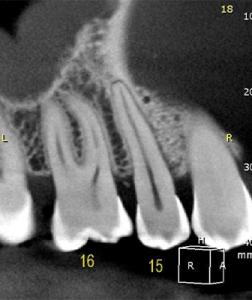

1 | Radiografia periapical inicial revelando uma lesão cística interradicular

2, 3 e 4 | Diferentes planos tomográficos, evidenciando a real extensão da lesão.